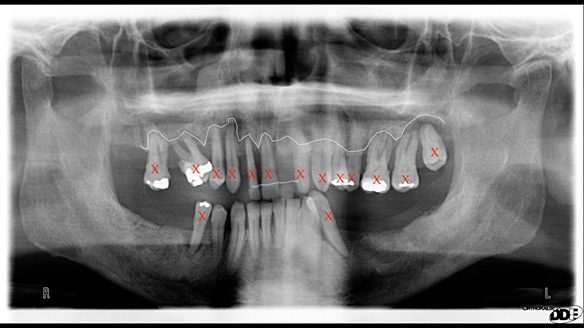

- Generalised periodontitis; stage IV grade C: currently unstable, risk factors: smoker.

- The remaining maxillary teeth had hopeless prognosis in the short term. They exhibited 80 - 100% alveolar bone loss with increased mobility (Grade 2 - 3).

- The lower right second premolar and lower left first premolar (LR5 LL4) had hopeless prognosis in the short term. They exhibited 80 - 100% alveolar bone loss with grade 3 mobility.

- The remaining mandibular teeth had approximately 30 - 50% alveolar bone loss with grade 1 mobility.